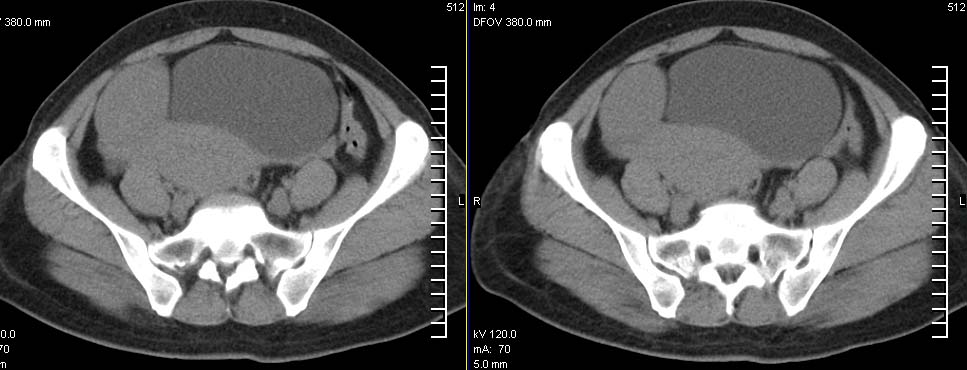

标题: CT9722:卵巢巨大占位,约10*18*21CM大小 [打印本页]

标题: CT9722:卵巢巨大占位,约10*18*21CM大小

卵巢巨大占位,约10*18*21cm大小

卵巢囊腺瘤可能性大.可见低密度

考虑:右侧卵巢囊性瘤可能性大 建议增强扫描。

肿瘤的密度有点高.和子宫差不多?且和子宫相连呢?我考虑来源于子宫,子宫巨大子宫肌瘤可能性大!(局部有坏死?)

考虑来源于卵巢的巨大占位,良性可能性大,内可见坏死区,建议强化检查。

右侧卵巢囊性瘤可能性大 ,5楼,密度不一样,是窗调得太宽

囊腺瘤不管是浆液性,还是黏液性的,液体成分应该占的比例很大吧!!这个病灶其实是个实性肿块,更看不到囊腺瘤所能见到的分隔??请笔者提供ct值?望大家再仔细分析??

右侧卵巢的巨大占位,病灶大部分呈实性,以恶性可能大。

右侧附件区巨大囊性肿块,边缘光滑,密度较高,左侧缘由多个低密度区,首先考虑囊腺瘤可能。